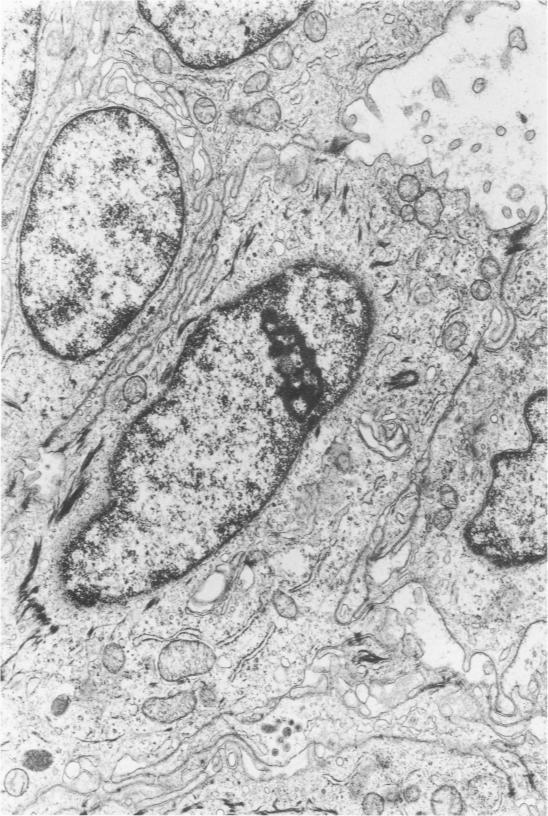

In this study, thymoma is defined as a neoplasm of the epithelial-reticular framework cells of the thymus. As in the normal thymus, these cells regularly displayed branching tonofilaments, macuale adherens, elongated processes, and basal lamina. These characteristics proved useful in the differential diagnosis of thymoma from a variety of anterior mediastinal tumors including thymic carcinoid, lymphoma, germinoma (seminoma type), and fibrous mesothelioma. Lymphocytes in the thymomas often showed mitotic activity and a moderate degree of transformation. The significance of this and the gland-like spaces, vacuolated epithelial cells, starry-sky appearance, emperipolesis, and perivascular spaces is discussed.